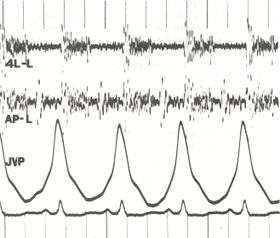

Other typical signs of pulmonary hypertension include an accentuated pulmonary component of the second heart sound, a right ventricular third heart sound, and parasternal heave indicating a hypertrophied right atrium. Signs of systemic congestion resulting from right-sided heart failure include jugular venous distension, ascites, and hepatojugular reflux.[5][6][9] Evidence of tricuspid insufficiency and pulmonic regurgitation is also sought and, if present, is consistent with the presence of pulmonary hypertension.[5][6][10]